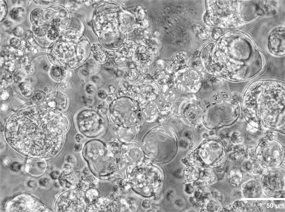

在肿瘤相关领域,赛箔与合作者共同研发基于生物3D打印技术构建的肿瘤微组织(PDT),涵盖十余个癌种,包括高发肿瘤、难治肿瘤、妇科肿瘤和儿童肿瘤,培养成功率超过了90%。通过近千例样本研究,证实PDT与患者组织具有高度一致的分子特征和药物敏感性,1-2周即可获得准确的药敏检测结果,为治疗赢取宝贵时间,并且可为新药研发企业提供药效评价、入组标准建立、适应症筛选等服务。在再生相关领域,赛箔已建立多种3D组织工程皮肤,包括表皮模型、全层皮肤模型、黑素皮肤模型等,并相应开发多种体外功效测试方法。